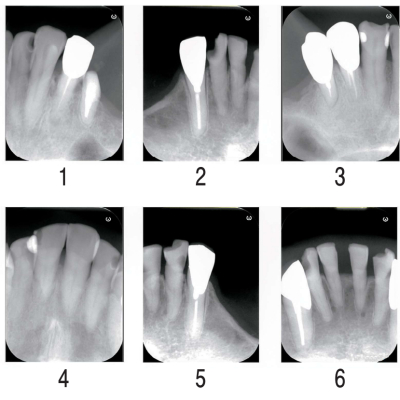

72 歳の男性。歯の動揺を主訴として来院した。イメージングプレートを用いて口内法エックス線撮影を行った。6枚のエックス線画像とエックス線画像配置のマッピングテンプレートを別に示す。

正しく読影できるのはどれか。1つ選べ。